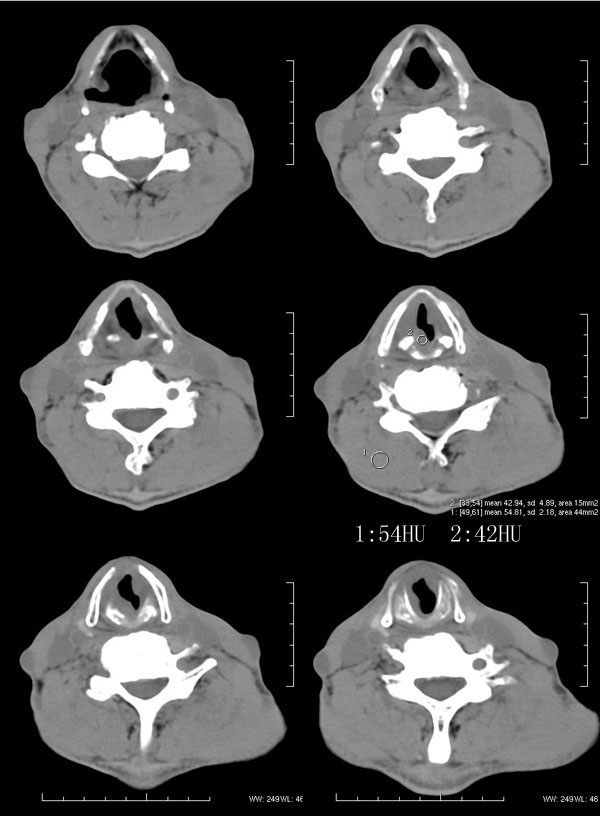

| 男性,57岁。反复声嘶1年,加重半年。 体检:喉粘膜充血,会厌肿胀,上举差,喉室及双声带窥视欠清。              蚂蚁发言:考虑喉癌(声门型)?双侧颈鞘周围淋巴结转移? 徐飞发言:有无呛水?根据病史要考虑球麻痹,脑干应检查 弯三角发言:考虑喉结核,应检查其它部位有无结核 卜一发言:喉腔右侧壁弥漫性软组织增厚,喉腔变窄。支持:喉癌(声门型)!另:双侧颈部多枚淋巴结肿大! 结果: 支纤镜检查:会厌板肿胀,右会厌咽侧壁肿胀,右杓状小结见结节样肿物,喉室肿胀,双声带肿胀、充血,左声带见菜花样肿物,触及易出血,取活检。 病理诊断:高分化鳞状细胞癌。 免疫组化:ck(h)(+++)、pcna(++)、p53(++)、ck(l)(-)。 原贴地址:http://www.radinet.com.cn/forum_view.asp?forum_id=4&view_id=34703 |